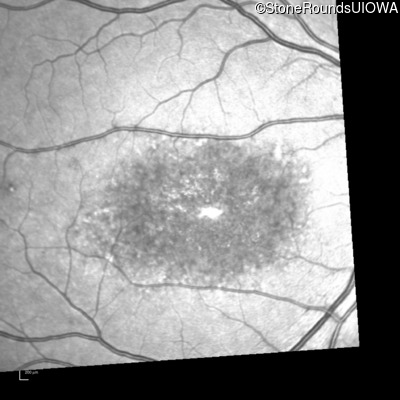

Blue Autofluorescence - Right - 10/125 -1

Exemplar